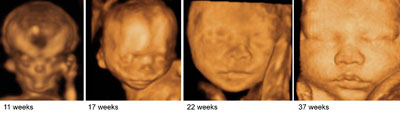

Fetal faces

Click the image to magnify it

Legend:Fetal faces

Reference(s):Rotten D, Levaillant JM. Two- and three-dimensional sonographic assessment of the fetal face. 1. A systematic analysis of the normal face. Ultrasound Obstet Gynecol 2004;23(3):224–31. PubMed PMID: 15027008.